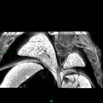

Caption Play MovieSerial 2D EFIC image stack in the coronal plane of 2346-004-3 (E16.5) shows pmVSD, mVSD, narrow DA

Copyright This image is from the Laboratory of Dr. Cecilia Lo, a member of the Cardiovascular Development Consortium (CvDC), Bench to Bassinet (B2B) program of the National Heart Lung and Blood Institute (NHLBI), and is displayed with the permission of the authors. J:175213

Mapk7b2b2346Clo mitogen-activated protein kinase 7; Bench to Bassinet Program (B2B/CVDC), mutation 2346 Cecilia Lo

Mapk7b2b2346Clo/Mapk7b2b2346Clo C57BL/6J-Mapk7b2b2346Clo